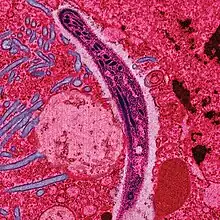

| False-colored electron micrograph showing a malaria sporozoite migrating through the midgut epithelium of a rat | |